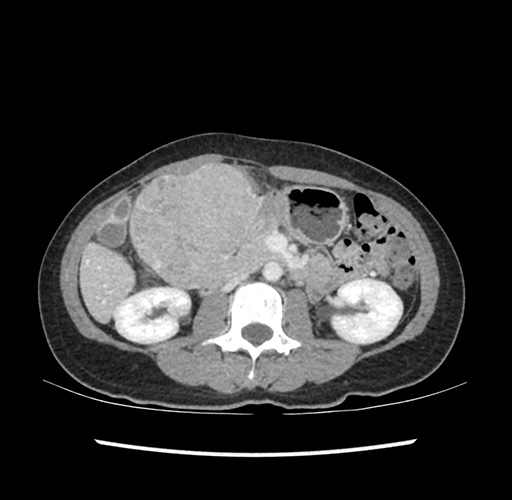

Imaging Analysis

Look through the patient's CT scan to identify any areas of concern for the necessary procedure.

Based on your CT findings, which issue(s) would give reason for "planned slowing down moment(s)" in this case?

Considering a standard left lateral sectionectomy procedure, what step(s) of the operation would you do differently in this case ?